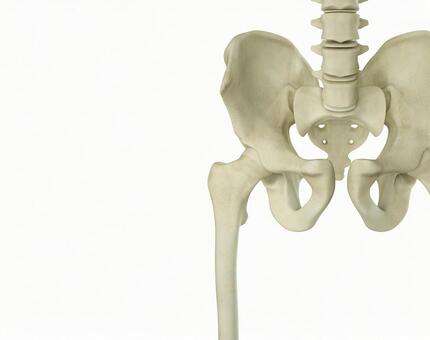

骨盤の歪みは、内臓が本来の位置より下がってしまったり、下半身の血流を悪くしたりする原因になります。

骨盤の歪みは以下の3種類に分けられます。

➀前傾タイプ

猫背になりやすく、胸やお尻の下垂、下腹部が出るという悩みを持つ人が多いです。

②後傾タイプ

反り腰になるため、背中・ももの張りや腰痛、便秘、生理痛、ししゃも脚の症状が出やすいです。

➂左右タイプ

骨盤の左右の高さにずれが生じやすく、肩こりや腰痛、O脚や足のむくみに悩む人が少なくありません。